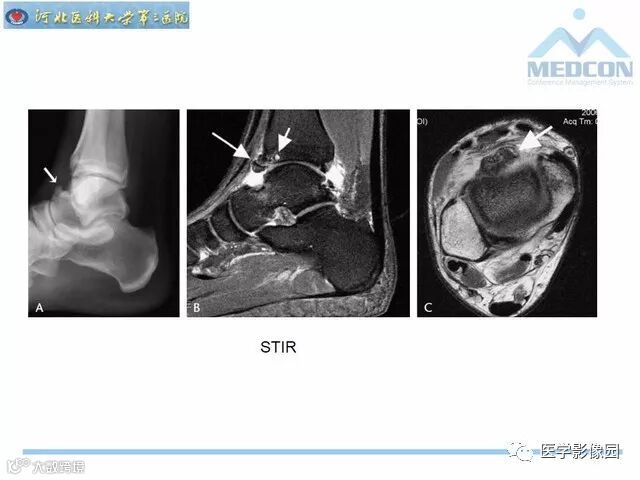

踝关节撞击综合征影像诊断,干货满满,值得收藏!

导读:踝关节撞击综合征影像诊断。干货满满,值得收藏!

踝关节撞击综合征影像诊断。干货满满,值得收藏!